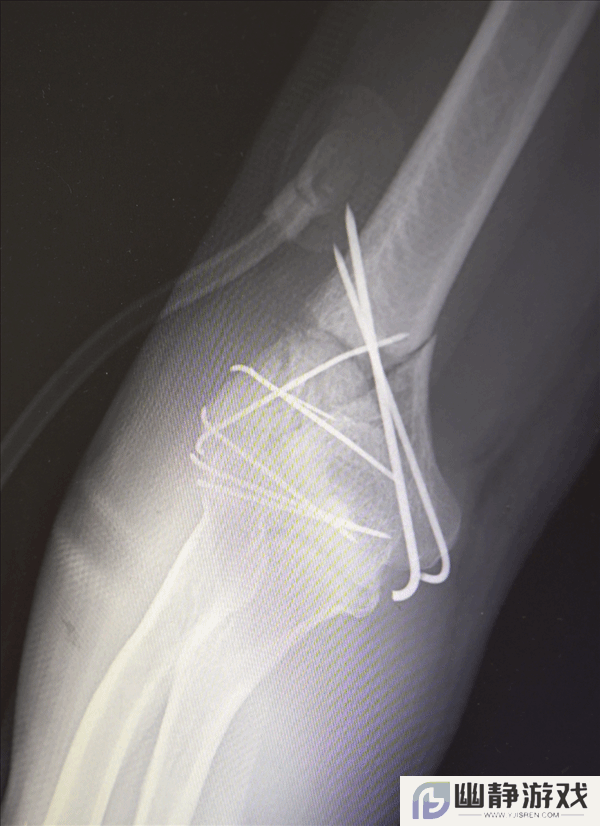

鉴于男子多处骨折,其中最严重的当属右肘部C3型粉碎性骨折,关节面及髁上严重粉碎(碎成了七块),肘关节易粘连,复位固定难度极高。

最终医疗团队采用了“拼古董”式复位固定技术,就像修复一件珍贵的古董瓷器,先拼接大块骨块再贴合小块,先后进行了两次手术。